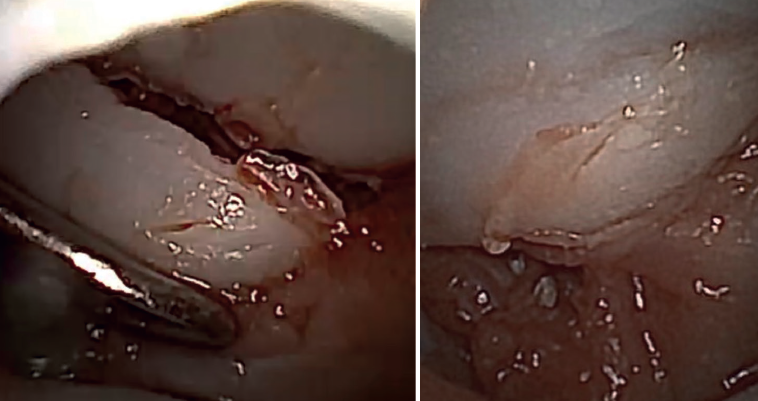

Evacuation of the hematoma and debridement of the perilesional tissue

We begin complete evacuation of the fracture hematoma and the synovectomy. This allows inspection of the joint and better identification of the fracture pattern, as well as correct visualization of all the structures.

Identification of the type of fracture and fixation of the fragments

Once vision has improved, we can begin to assess the fracture pattern and can determine the plan for reduction and fixation.

The free osteochondral fragments can be removed with grasping or mosquito forceps.

The main fragments are reduced with the aid of a palpator or a small blunt dissector. External reduction of the fragments may be necessary, especially when they are impacted in the centre of the articular surface. This is especially common at the base of the proximal phalanx. To do this, we introduce a 1.0 Kirschner wire through the fracture site, through an extra-articular "window", and in "joystick" fashion, we lower the impacted fragment. Sometimes it is advisable to check each of the maneuvers using fluoroscopy, which can be positioned perpendicular to the arm or in the traditional manner, which requires us to release the hand of the patient in order to perform the check.